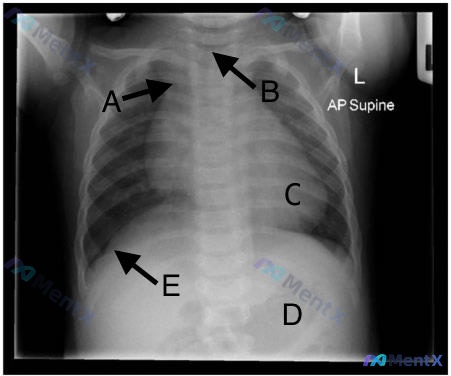

整理了一个很有意思的儿科影像教学病例,分享一下思路: 病例概况 - 患儿:6个月大女婴 - 就诊原因:例行体检 - 既往史:6周前因细菌性肺炎住院,阿莫西林治疗后完全康复 - 现状:发育正常(能翻身、独坐、咿呀发音),添加糊状麦片,偶有吐奶,出牙期烦躁,生命体征平稳,体检无异常 - 影像资料:4周前...